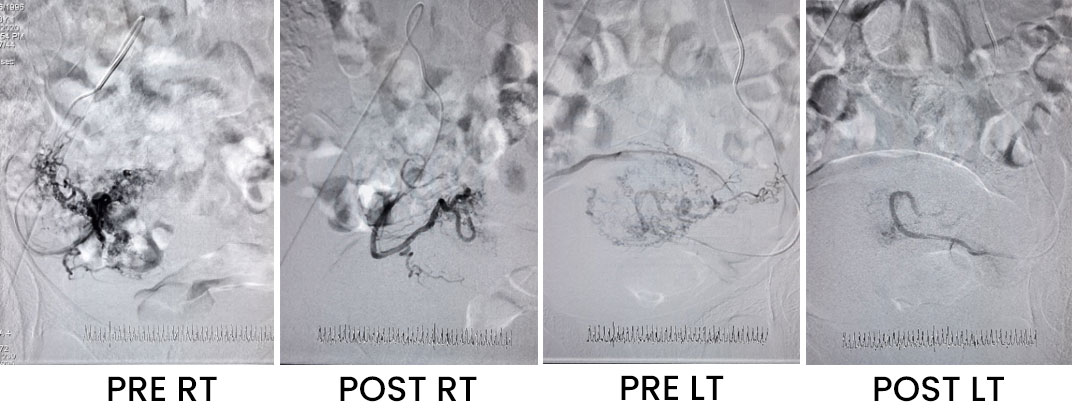

This interventional procedure is a boon for females who are suffering from heavy bleeding during their menstrual periods. A few common reasons for this are fibroids, and adenomyosis.

It gives almost complete relief from the symptoms of cramps like pain & excessive bleeding during the menstrual cycle. We have reported normal pregnancy after uterine artery embolization In a few of our cases done by a few of the cases done by us. Though the data on this is not yet adequate and hence the role of uterine artery embolization in nulliparous women is guarded.